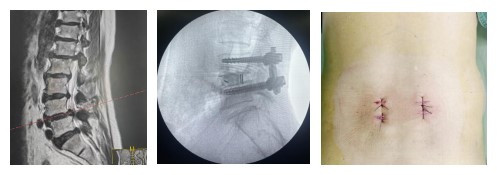

经过严谨的术前讨论和充分的准备,2025年4月1日,他为患者施行了“颈后路枢椎骨折切开复位内固定术”。手术台上,他目光如炬,手法稳如磐石,在放大镜与神经监测仪的辅助下,小心翼翼地避开重要的神经与血管,成功将移位的骨折块精准复位并牢固固定。当监测仪上显示患者神经功能一切正常时,手术室内所有人都松了一口气。术后第三天,患者便在支具保护下开始下床活动,并于4月14日康复出院,重新挺直了脊梁。